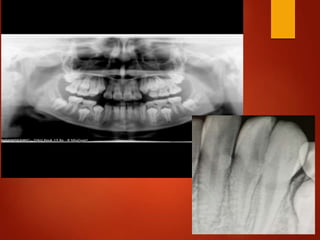

El documento es un registro médico odontológico que muestra las fechas de las visitas de un paciente al centro de salud El Raval, incluyendo exámenes y tratamientos realizados como la extracción de cálculos salivales en abril y mayo de 2012.